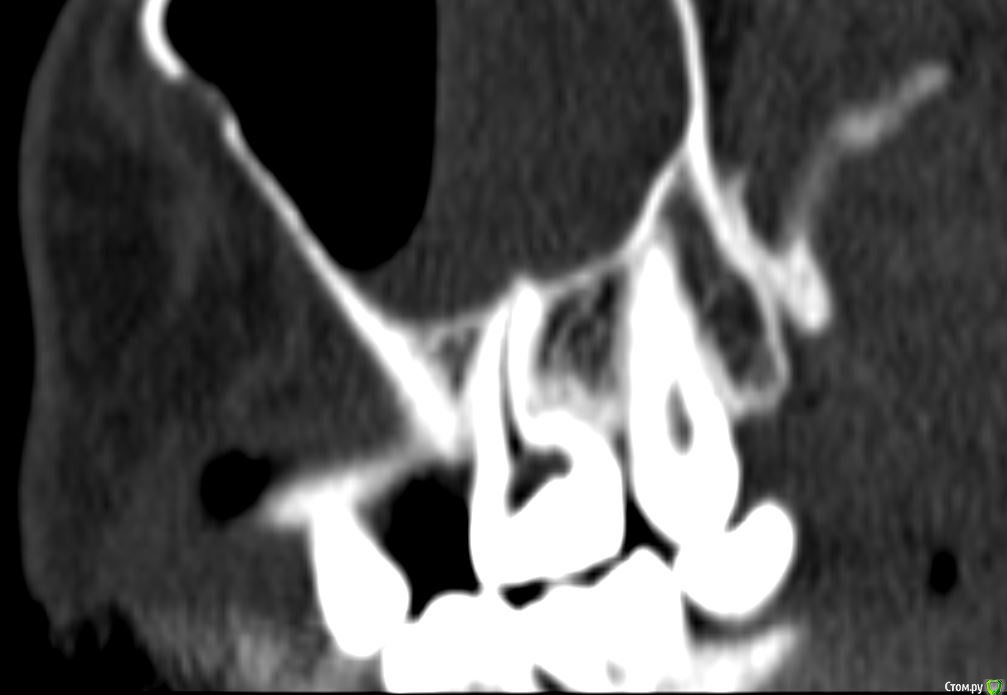

Лисица Опубликовано 26 июля, 2015 Автор Поделиться Опубликовано 26 июля, 2015 (изменено) Вы же не думаете, что Вам назначат а/б терапию по интернету? Я просто не знаю, исходя из каких показателей она назначается. Поэтому осведомилась на всякий случай. Итак, сходила я сегодня на КТ. И по ходу мне сделали что-то не то... Когда я обратилась в клинику, я уточнила, что мне нужно КТ для эндодонтии, чтобы видно было каналы, с достаточным разрешением, чтобы было видно зубы и их корни, входящие в верхнечелюстной синус. Администратор клиники уточнила у врача и сказала, что мне нужно заказывать не КТ верхней челюсти, а КТ пазух. У рентгенолога я также повторила все описанное, рассказала, что при лечении каналов вчера была продырявлена пазуха, уточнила, будут ли видны как следует зубы и их каналы, меня заверили, что "все будет". Причем у врача, судя по описанию на сайте клиники, была ординатура по хирургии в медико-стоматологическом университете, так что он, уж наверное, понимал, что мне нужно. В итоге я получила пленку со снимками формата чуть ли не А3 и диск. На пленке все зубы были просто белыми и коронки видны не целиком. Заключение: в правой верхнечелюстной пазухе уровень жидкости, острый правосторонний гайморит.Думала, может в программе можно будет увеличить разрешение. Но похоже, что нет... или я просто ламер? Зубы просто размытые и белые... Прилагаю сделанные мной скриншоты, как мне кажется, наиболее показательные... Если нужно другие "виды", то скажите какие, или такие снимки вообще ни о чем? Программа просмотра называется Philips DICOM Viewer R3.0-SP03. Аппарат был не местный "на голову", а здоровый, куда заезжаешь в лежачем положении. Изменено 26 июля, 2015 пользователем Лисица Ссылка на комментарий

Лисица Опубликовано 26 июля, 2015 Автор Поделиться Опубликовано 26 июля, 2015 Тьфу ты, Акелла промахнулся. Не та сторона в профиль. Вот парочка проекций с нужной больной стороны. Ссылка на комментарий

St. Опубликовано 27 июля, 2015 Поделиться Опубликовано 27 июля, 2015 Гайморит справа есть, и жидкость тоже. Корни этого зуба действительно заканчиваются в гайморовой.Ничего такого страшного, чтоб однозначно удалять зуб я не вижу. С гайморитом - к лорам на лечение.В зубе я бы ещё раз поменяла лекарство на пару недель, пока гайморит не притихнет, потом постоянно пломбировать. 1 Ссылка на комментарий

Лисица Опубликовано 27 июля, 2015 Автор Поделиться Опубликовано 27 июля, 2015 St., большое спасибо за ответ! Моя врач планировала закрыть его в среду (зная о том, что пазуха проткнута). Если запломбировать, пока воспаление есть, какие могут быть проблемы? И еще она сказала, что нащупала 4-й тонкий канал, но не было времени его прочистить, так что она оставила как есть до среды. Сказала, что почистит и сразу же закроет. Судя по КТ, корня 3, значит в одном из них 2 канала? В 3D похоже, что корни с медиальной стороны сросшиеся какие-то... и на небном тоже борозда. Ссылка на комментарий